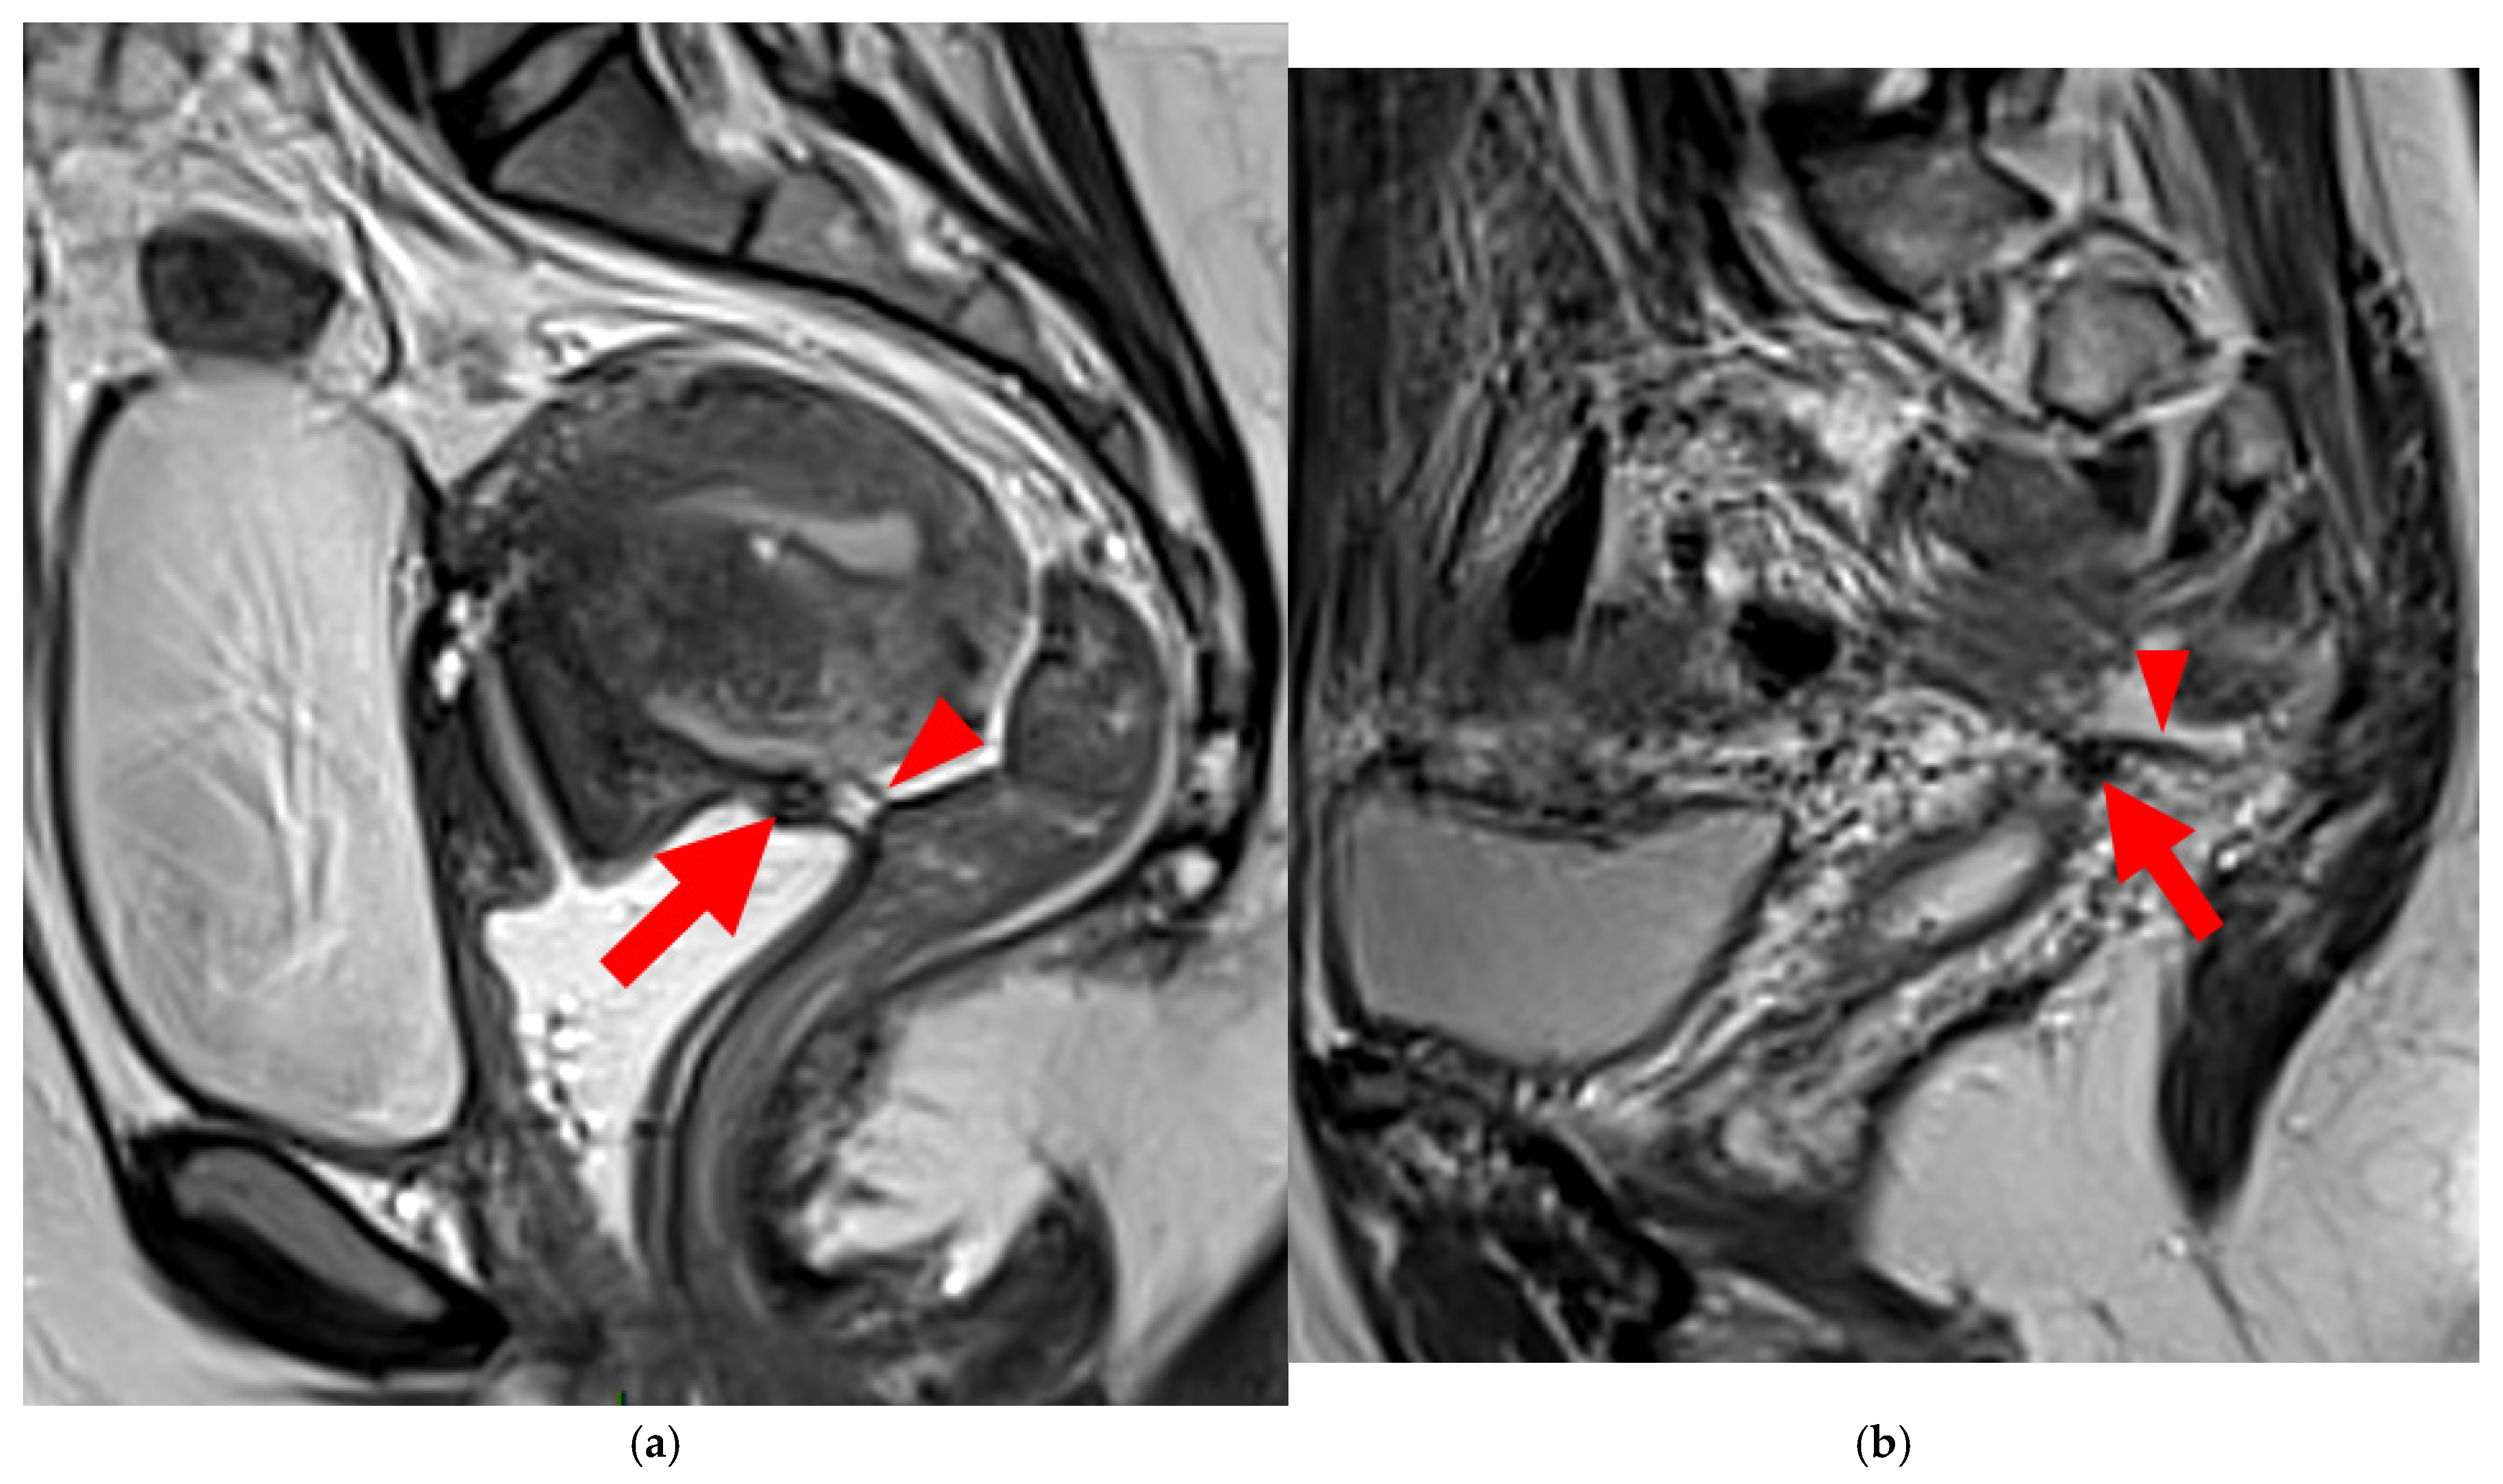

A type 3B USL (Figure 4), in addition to being thickened, has a notched surface with slightly irregular margins, or a caliber disparity with focal thickening, or appears “stiffened”, which means it loses its curvilinearity to exhibit a steep vertical orientation in the sagittal plane or a “bowstringing” of the USL in the sagittal or axial planes. Occasionally, a USL might appear thin but “stiffened”, which would upgrade it from a type 2 to a type 3B.

Figure 4. Pelvic MRI scans of seven patients with HTD type 3B USLs. (a) Sagittal T2WI: a thickened (2.1 mm) and stiffened right USL (arrowhead) with “bowstringing”. (b) Axial T2WI: a caliber disparity (dashed arrows) with focal thickening (4.2 mm) of the left proximal USL (arrowhead). (c) Sagittal T2WI: a caliber disparity (dashed arrows) with focal thickening (2.5 mm) of the right distal USL. (d) Axial T2WI: a right USL with a notched and irregular surface (dashed arrows). (e) Axial T2WI: thickened and stiffened left (3 mm) and right (2.5 mm) USLs with “bowstringing” of both USLs (arrowheads). (f) Sagittal T2WI: a thickened (2.6 mm) right USL with a stiffened appearance characterized by a steep vertical orientation (arrowhead). (g) Sagittal T2WI: the right USL appears thin (1.9 mm) but stiffened (arrowhead), exhibiting “bowstringing”. These findings led to its reclassification from type 2 to type 3B.